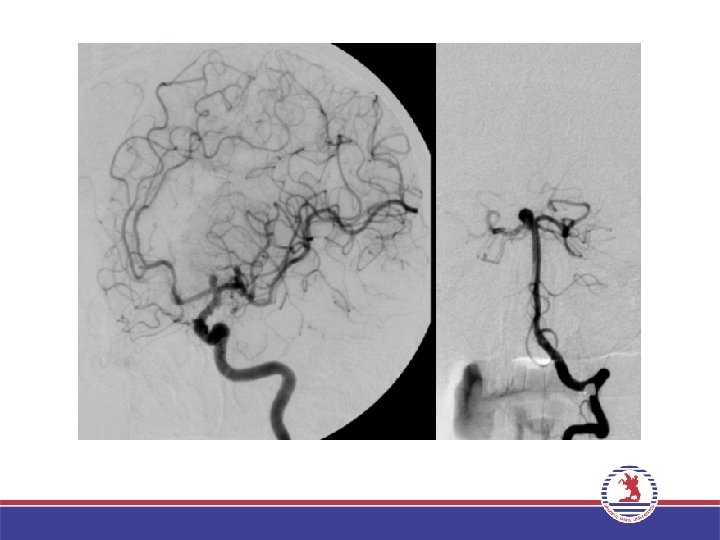

SEREBRAL ANJİYOGRAFİ

SEREBRAL ANJİYOGRAFİ Endikasyonlar Subaraknoid kanama nedeninin araştırılması – Anevrizma (+tedavi planlaması) Preoperatif tümör vaskülarizasyonunu değerlendirme Çeşitli serebrovasküler hastalıkların araştırılması Arteriyovenöz malformasyon Venöz tromboz Vaskülit Akut inme tanı ve tedavisi

SEREBRAL ANJİYOGRAFİ Teknik Projeksiyonlar: Ön-arka (Town) Oblik Lateral 4 fazlı görüntüleme yapılır. Arteryel faz Parankimal faz Kortikal venöz faz Dural sinüs fazı İşlemler karşı taraf için tekrarlanır.